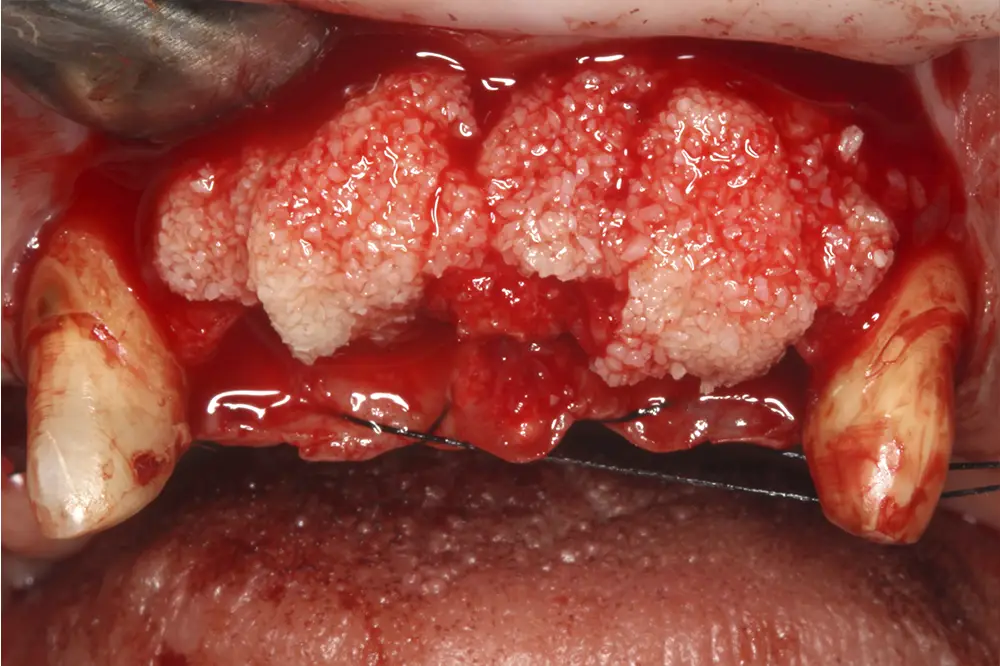

En estas zonas de atrofia horizontal extrema, utilizamos, además de los implantes anteriormente descritos, una técnica para su colocación que consiste en la compactación y expansión del volumen óseo residual, lográndose una correcta estabilidad primaria y preservándose al máximo el volumen óseo residual en las paredes del neoalveolo. Este procedimiento se lleva a cabo con los expansores motorizados y la colocación final del implante como último expansor. Además, podemos realizar sobre la tabla vestibular una sobrecorrección final con hueso autólogo obtenido del fresado o con un rascador óseo de zonas adyacentes y finalizar con una capa de biomaterial sobre el hueso autólogo25,29,36,37,48,49. De este modo se logra una cresta de mayor anchura con un procedimiento mínimamente invasivo (fig. 17). Finalmente, en la zona distal del primer cuadrante, adyacente al molar que será extraído y regenerado su alveolo con PRGF-Endoret, se planifica un implante corto de 6,5 mm de longitud y 3,3 mm de diámetro de forma directa para evitar realizar una elevación de seno a este nivel (fig. 18).

Una vez realizada la planificación de forma exhaustiva, y analizadas las técnicas quirúrgicas e implantes que se van a emplear en cada zona del maxilar superior, se procede a la cirugía de implantes. Para realizar una inserción de los mismos guiada a través de la prótesis, se confecciona una guía quirúrgica que nos sirve de referencia durante la cirugía, que se posicionará en los caninos superiores que se deciden mantener para la fase de provisionalización del paciente (figs. 19-22). Tal como se ha explicado, podemos observar en las imágenes de la cirugía la sobrecorrección que se lleva a cabo de las zonas con mayor atrofia a nivel horizontal (figs. 23-24). Tras la cirugía, los implantes se dejan en dos fases quirúrgicas, debido al empleo de técnicas accesorias y se coloca un provisional sobre los dos caninos que se conservan temporalmente (figs. 25-26). Estos caninos que se conservan se tratan mediante tratamiento periodontal quirúrgico para una mejor cicatrización postoperatoria y alargar la vida de los mismos el tiempo que se necesita para los provisionales.

Figs. 23 y 24. Sobrecorrección posterior según el protocolo anteriormente descrito, donde se coloca el hueso autólogo con PRGF-Endoret en la capa basal y el biomaterial en la superior. Posteriormente, se cubre todo con membranas de fibrina autóloga retraídas y se sutura sin tensión con un monofilamento 5/0.